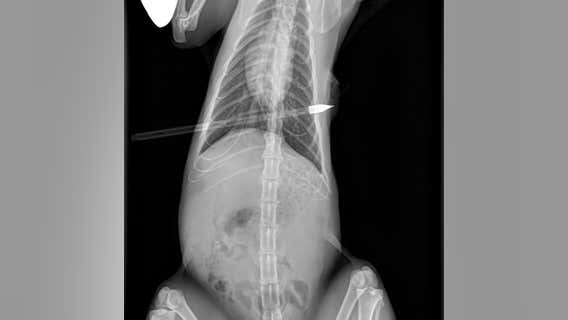

Cat found with arrow in it rescued by Dearborn police

There is a $1,000 reward for information that leads to the arrest and conviction of the perpetrator involved in the animal abuse.